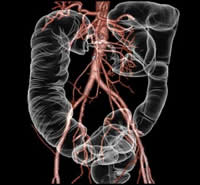

検査は、ベッドに寝ているだけで終了します。また、当院検査は、一回の撮影で同時に複数の輪切り像が得られる最新型ボリュームCTスキャナです。 得られた輪切り画像から下のような精密な立体像を作ることも可能です。

体幹部3次元画像